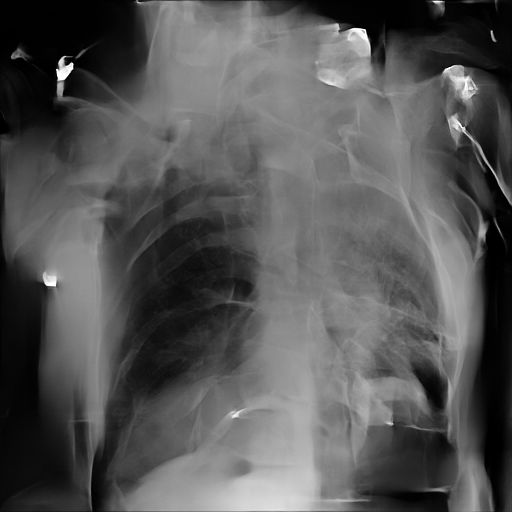

In Fig. 1, we show four ϵitalic-ϵ\epsilon-LDP-processed CXR images of clinical cases obtained with the image domain LDP, which directly imposes the Laplace mechanism on the input image, with different privacy budgets together with the original images. Fig. 2 shows four ϵitalic-ϵ\epsilon-LDP-processed CXR images of clinical cases obtained with DP-GLOW and different privacy budgets together with the original images. In case 1 for DP-GLOW, there is decreased permeability in the bilateral hilar regions. Although this hilar opacity tends to be preserved with a larger privacy budget, the entire image is degraded when the privacy budget becomes 101HWsuperscript101𝐻𝑊10^{1}\cdot H\cdot W. A similar tendency is observed in the images of all the four cases for DP-GLOW; for example, in case 4 with ϵ=101HWitalic-ϵsuperscript101𝐻𝑊\epsilon=10^{1}\cdot H\cdot W, the lung opacity suggesting pneumonia in the right lower lung field is well preserved, while the entire image is degraded.